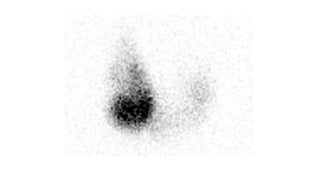

Grave’s Disease

• Varying degrees of

thyromegaly with

uniform

distribution of

increased activity.